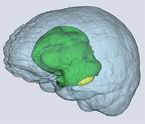

Fokus der Anwendung ist, eine hochpräzise dreidimensionale Segmentierung von bösartigen Hirntumoren, wie Glioblastomen, durchzuführen.

Nach erfolgreichem Training wird das optimierte neuronale Netzwerk in die interaktive Anwendung integriert, die dann in der Lage ist, neue, zuvor nicht bekannte MRT-Bilddaten zu segmentieren und auszuwerten.